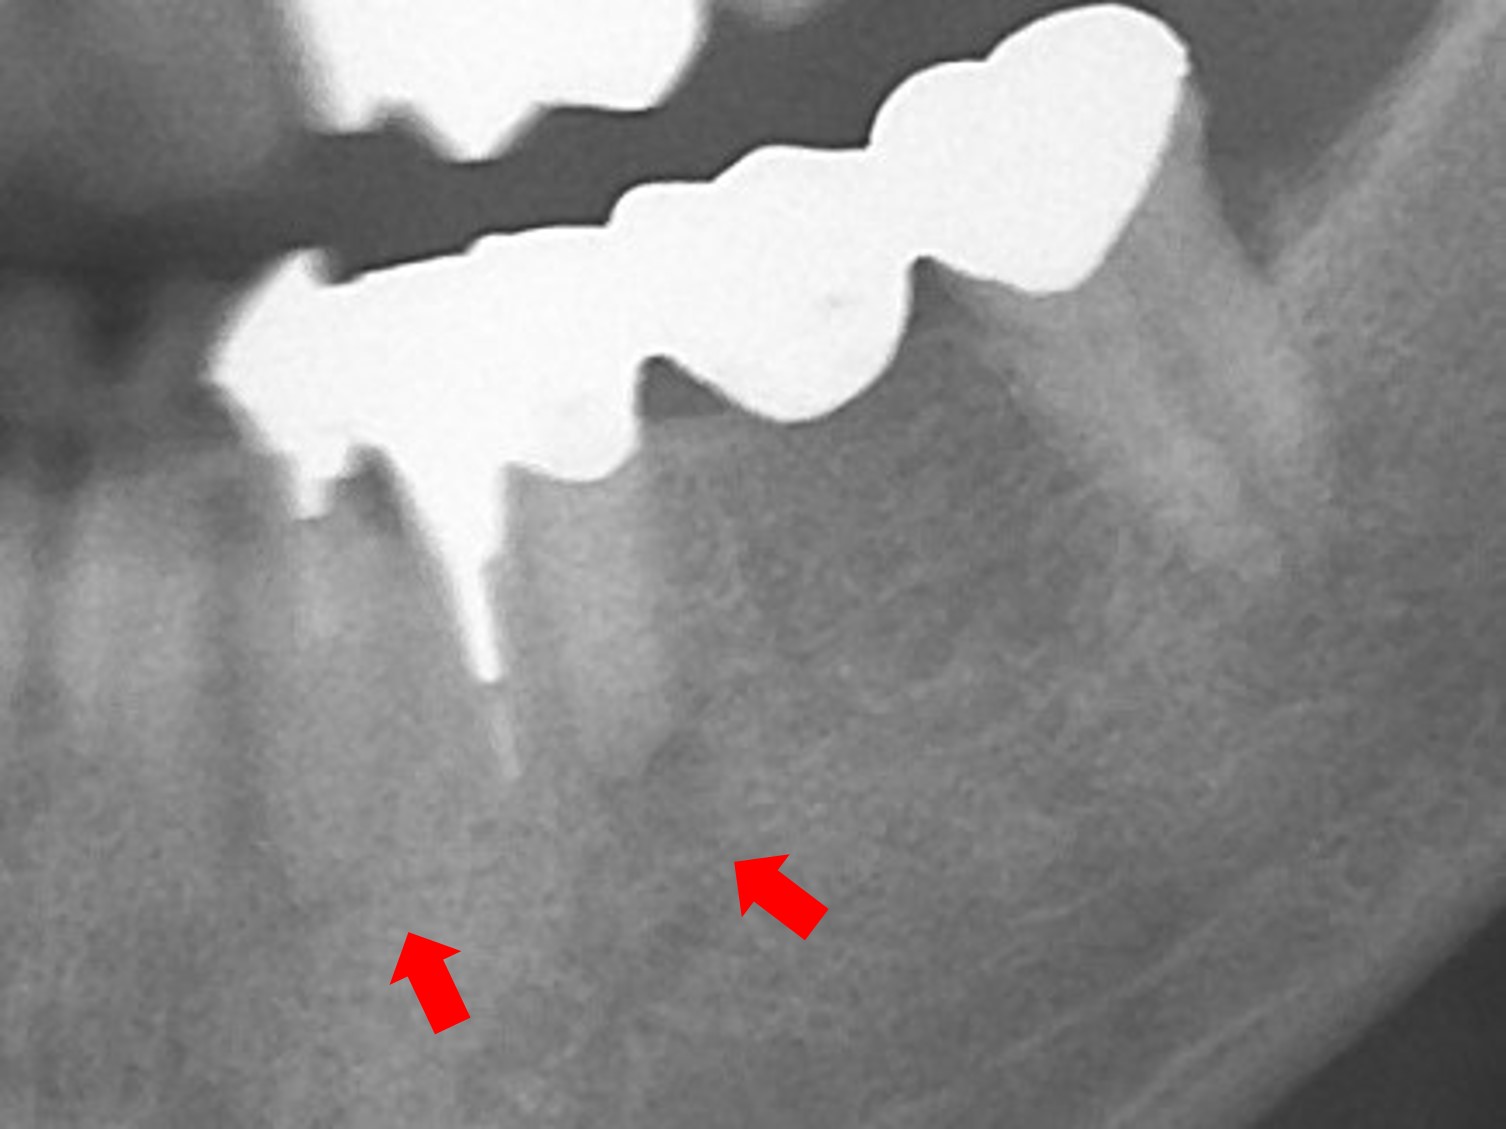

- 最終補綴を最重要と考え、骨質、骨幅、高さなども考慮してインプラント埋入位置を決定するが、下顎管との距離、それを避けるためのインプラントの選択、位置、深さ、角度を診断することが重要である。

左側下顎犬歯(#33)ならびに第2小臼歯(#35)の根尖性歯周病による保存不可と第1大臼歯欠損(#36)抜歯後2か月での待機埋入症例

骨造成を伴う症例